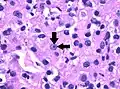

![]() Типичная гистологическая картина светлоклеточного рака почки в высоком разрешении. Окраска гематоксилином и эозином. | |

Клетки светлоклеточного рака почки обычно имеют светлую, прозрачную цитоплазму, хорошо различимую клеточную мембрану, и содержат шарообразное, более или менее обычно выглядящее, ядро[2].

Светлоклеточный рак почки высокой (3-й) степени злокачественности. Окраска гематоксилином и эозином. Увеличение в 100 раз. Стрелочки указывают на чётко видимое ядрышко клетки.